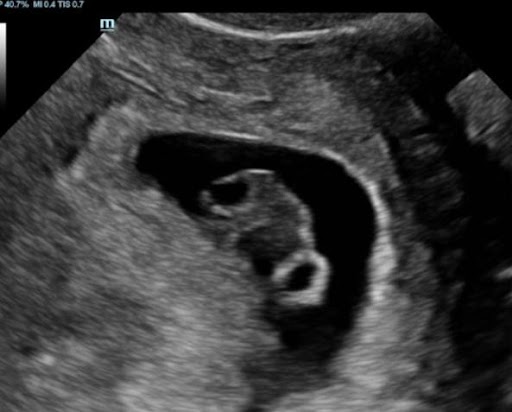

2D ultrasound scan: The Medical Standard

These scans are crucial for diagnostic purposes.  While essential for medical care, 2D images can Sometimes it can be challenging for untrained eyes to decipher.Despite being simple, 2D scans are highly effective and widely used throughout pregnancy.